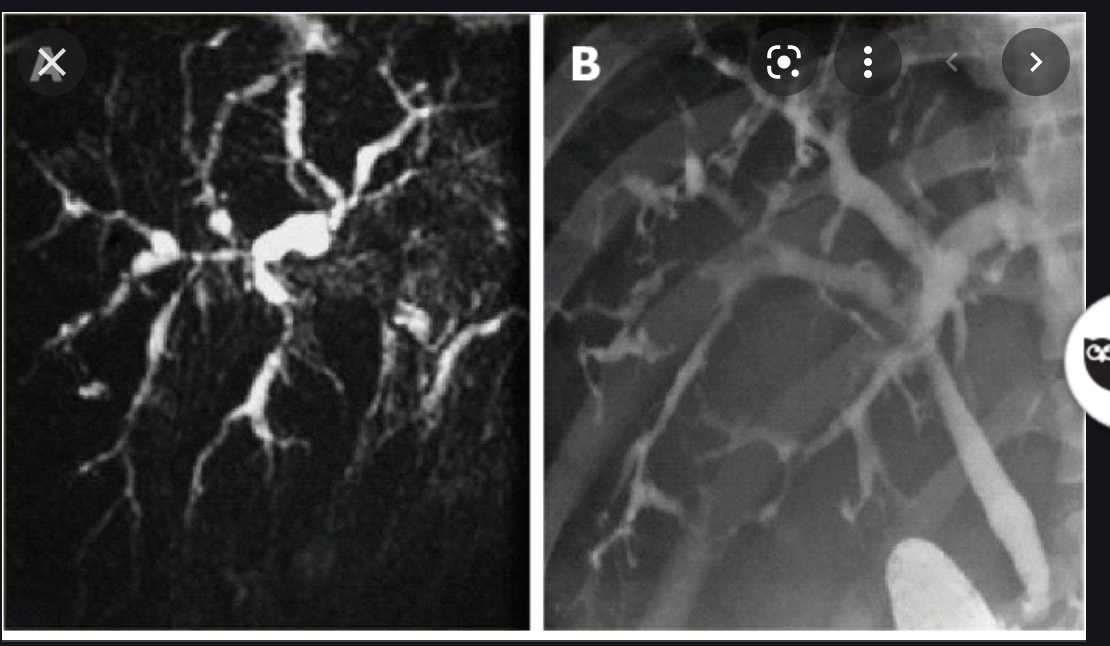

What is MRCP

- Fat sat T2 imagines of the upper abdo

- bile is hyper intense

- images of the biliary and pancreatic ducts can be rendered by maximum signal intensity projection recons (MIPS)

- Common indications

- unsuccessful ERCP

- ERCP contraindicated

- biliary-enteric anastomoses

- chledochojejunostomy

- billroth II

What are the Imaging features of Sclerosing Cholangitis?

- Irregular dilatation

- stenosis

- beading of intrahepatic and extrahepatic bile ducts (seen best on cholangiogram)

- string of beads appearance

- small ‘diverticula’ of biliary tree are PATHOGNOMONIC